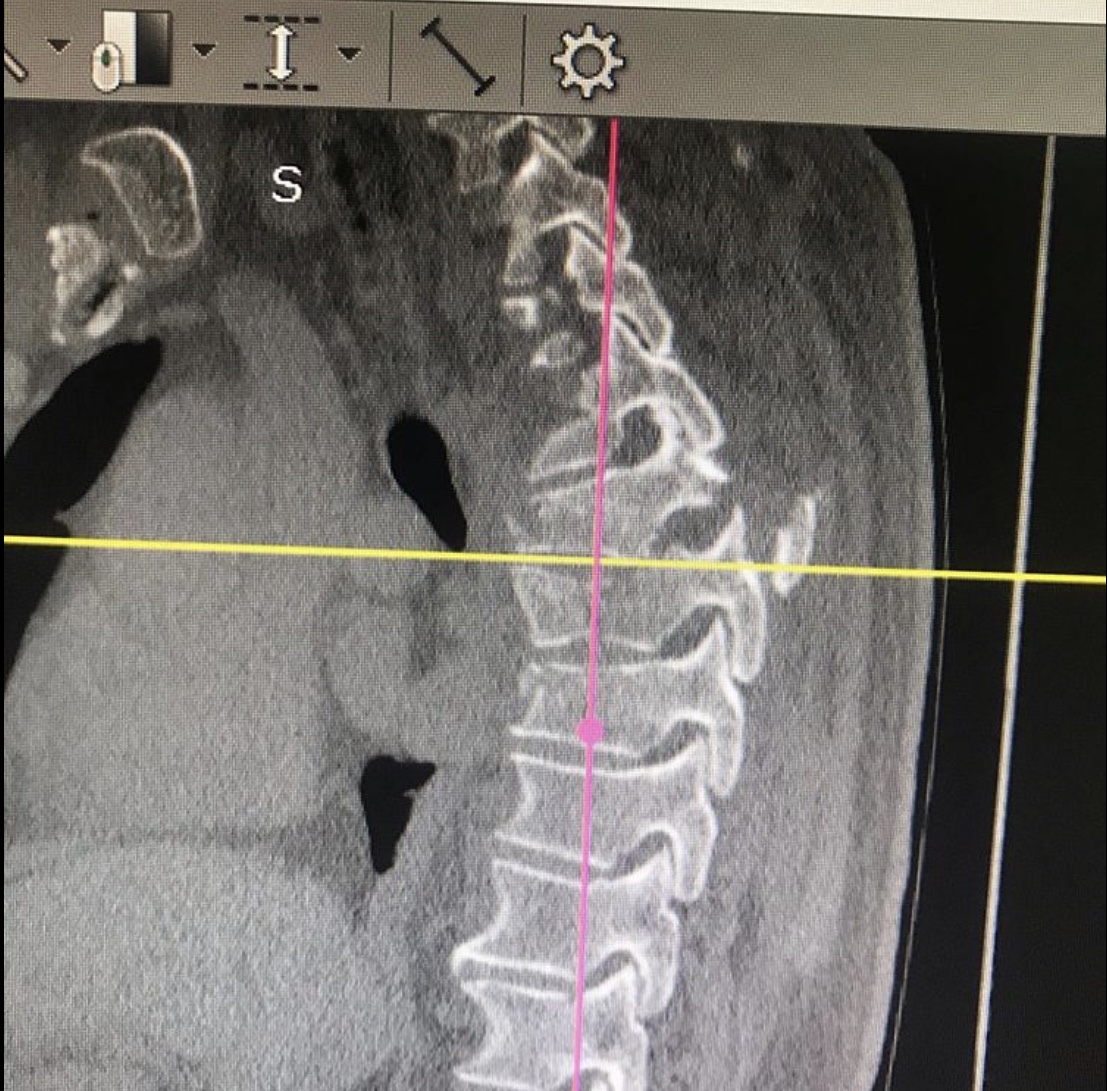

Пациент с нестабильным переломом грудных позвонков, с переломом суставных отростков был экстренно доставлен в Городскую клиническую больницу № 7 Казани. Как сообщает врач – травматолог – ортопед клиники Руслан Ильгизарович Закиров, переломы в данном отделе опасны своими тяжелыми осложнениями, которые представляют угрозу для жизни пациента. Особенно, если они единовременно сочетаются с дополнительными поражениями связок, хрящей, мышц, спинного мозга, нервных структур, кровеносных сосудов и внутренних органов.

После тщательного обследования пациенту была выполнена реклинация и задняя стабилизация транспедикулярной системой: транспедикулярный спондилодез Д3-Д10.